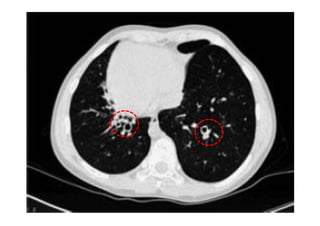

Utiliza-se com frequência p/ avaliar:

Alterações patológicas e diagnóstico de pneumopatias;

Radiografia e TC de tórax

Utiliza-se com frequênciap/ avaliar: O posicionamento do TOT: 4-6 cm acima da carina; Se os pulmões estão sendo aerados adequadamente; Alterações patológicas e diagnóstico de pneumopatias; Outros. Radiografia e TC de tórax